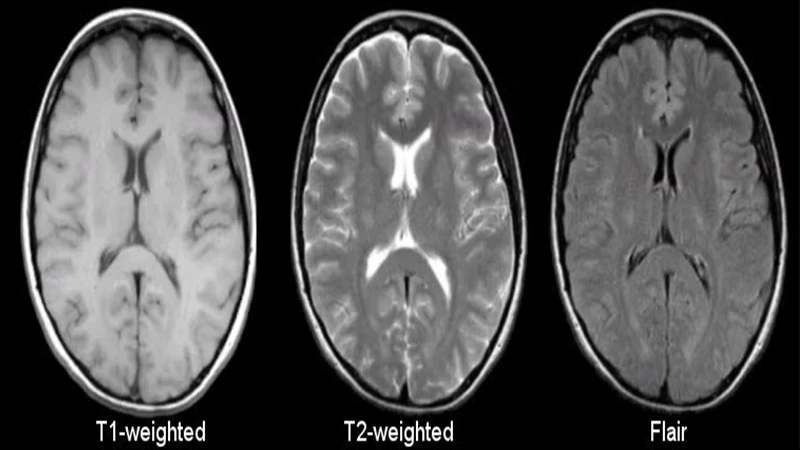

The Language of MRI: T1 and T2 Weighting

The process of protons relaxing back into alignment occurs in two distinct ways, known as T1 and T2 relaxation. By adjusting the timing of the RF pulses and listening for the signal, technologists can create images that emphasize one type of relaxation over the other. This is called "image weighting."

• T1-Weighted Images: In these images, tissues that relax quickly (like fat) appear bright. Tissues that relax slowly (like water and cerebrospinal fluid) appear dark. T1 images are excellent for visualizing normal anatomy and the structure of organs.

• T2-Weighted Images: In these images, tissues that relax slowly (like water and fluid) appear bright. This makes T2 images extremely sensitive for detecting pathology, as many diseases—like tumors, inflammation, and trauma—result in an increase in water content.

Side-by-side comparison of a T1-weighted and a T2-weighted MRI of a human brain, showing differences in fluid brightness